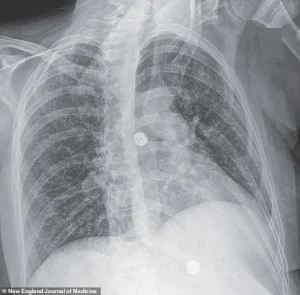

Over the course of her hospitalization, medical professionals observed a troubling progression: a persistent, dry cough that worsened over time, accompanied by declining oxygen levels and labored breathing.

X-ray scans conducted during her stay uncovered small nodules in her lungs, a finding suggestive of bacterial infection.

In its early stages, the disease often presents with a persistent, unexplained cough, sometimes accompanied by coughing up blood or chest pain.

Patients may also experience unexplained weight loss, loss of appetite, fever, and night sweats.

If left untreated, the infection can progress to severe respiratory failure, extensive lung damage, and even the spread of bacteria to other organs, such as the brain, liver, and pancreas.